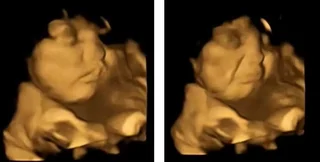

Реакція малих на моркву

Фото: реакция на морковь

Так, у 100% випадків малюки мам, які отримали капсулу з броколі, кривилися та хмурилися. Водночас малюки, чиї мами з'їли моркву, виглядали щасливими та усміхненими. Отримані результати, на думку вчених, свідчать про те, що харчові звички починають формуватися ще в утробі матері, коли ми вперше "пробуємо" ті чи інші смаки.